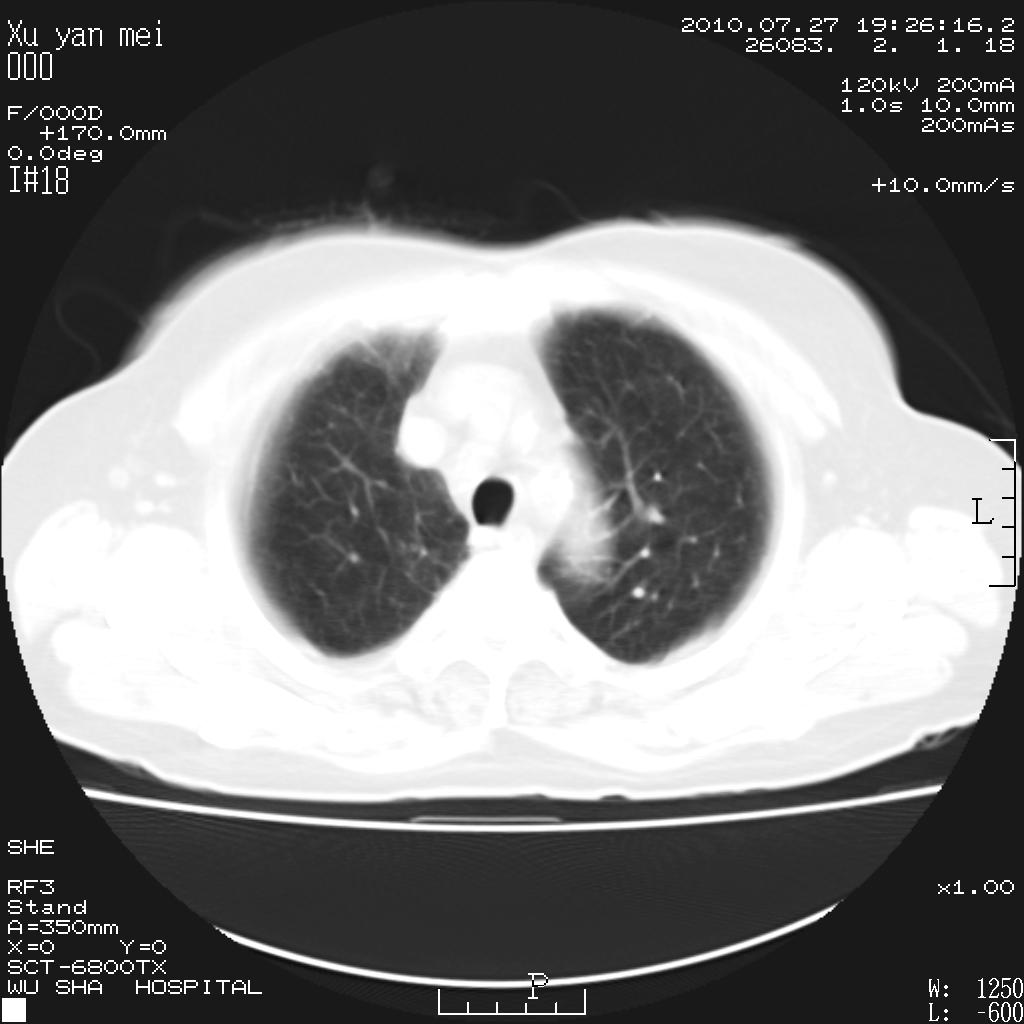

女,60岁,胸痛就诊,右肺结核?炎症?其它?(胸片右侧中上肺野确实看不到什么啊)

1)考虑两肺感染性病变;建议抗炎治疗后复查。2)双侧少量胸腔积液。

1)考虑两肺感染性病变;建议抗炎治疗后复查。2)右侧少量胸腔积液。

双肺炎症可能性大,建议抗炎后复查。右侧胸腔少量积液。双侧胸膜轻度增厚。

考虑两肺感染性病变;不除外肺栓;建议抗炎治疗后复查。